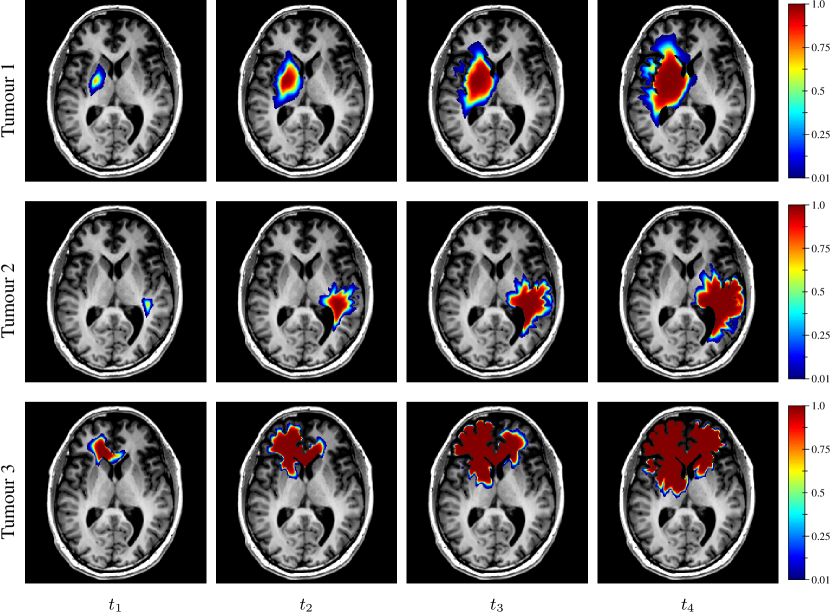

For each synthetic tumour, a tumour cell diffusion tensor field 𝑫(𝒓)𝑫𝒓\boldsymbol{D}(\boldsymbol{r}) was then obtained by multiplying the unit (unscaled) diffusion tensor derived as described in Section 2.3.6 by the derived value of dwhitesubscript𝑑whited_{\rm white}. As a remainder, the ratio dgrey/dwhitesubscript𝑑greysubscript𝑑whited_{\rm grey}/d_{\rm white} was considered constant among tumours in this work (see Section 2.3.6). A tumour was finally grown from the sampled seed, tumour cell diffusion tensor field 𝑫(𝒓)𝑫𝒓\boldsymbol{D}(\boldsymbol{r}), and proliferation rate ρ𝜌\rho using the model and the simulated tumour cell distributions at times t14subscript𝑡14t_{1-4} were stored. Examples of synthetic tumours are depicted in Figure 4. The corresponding model parameter values are provided in Table 2.

Refer to caption

Figure 4: Examples of simulated tumour cell density distributions at times t14subscript𝑡14t_{1-4} (1st to 4th columns, axial slices) from the MR data of the same subject as in Figures 1 and 2. The corresponding model parameter values are provided in Table 2.

Table 2: Parameter values used for the tumour simulations in Figure 4.

𝒅𝐰𝐡𝐢𝐭𝐞subscript𝒅𝐰𝐡𝐢𝐭𝐞\boldsymbol{d_{\rm white}} [mm2 yr1timesmillimeter2year1{\mathrm{mm}}^{2}\text{\,}{\mathrm{yr}}^{-1}] 𝝆𝝆\boldsymbol{\rho} [yr1year1{\mathrm{yr}}^{-1}] 𝝀𝝀\boldsymbol{\lambda} [mmmillimeter\mathrm{mm}] 𝒗𝒗\boldsymbol{v} [mm yr1timesmillimeteryear1\mathrm{mm}\text{\,}{\mathrm{yr}}^{-1}] 𝒕𝟏subscript𝒕1\boldsymbol{t_{1}} [dday\mathrm{d}] 𝒕𝟐subscript𝒕2\boldsymbol{t_{2}} [dday\mathrm{d}] 𝒕𝟑subscript𝒕3\boldsymbol{t_{3}} [dday\mathrm{d}] 𝒕𝟒subscript𝒕4\boldsymbol{t_{4}} [dday\mathrm{d}]

Tumour 1 10.87 31.77 1.71 37.16 175 328 418 508

Tumour 2 15.07 13.95 0.96 29.00 146 316 406 496

Tumour 3 41.49 11.31 0.52 43.33 137 242 332 422